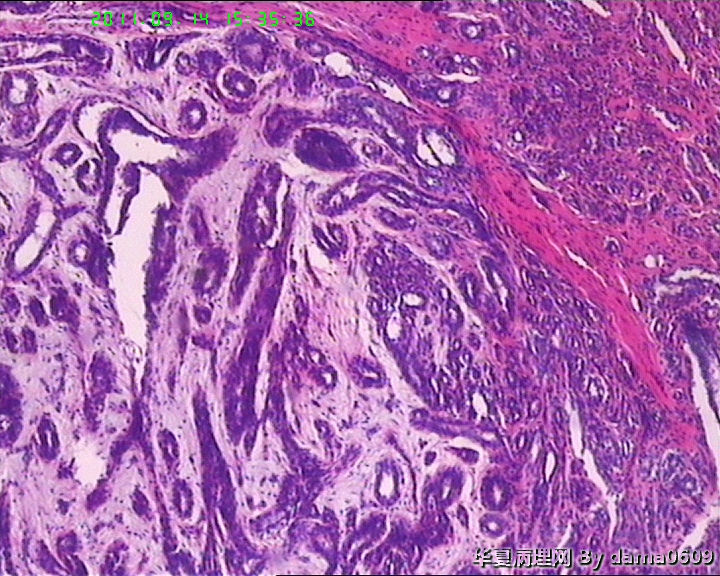

女,22岁,乳腺肿物,病史不详。

不整形软组织肿物一个,V:2.0x1.5x1.5cm。无包膜。切面实性,灰白色,小结节状,质中。

镜下结构复杂,图3、4、8、10、11、12、13、15、17、18、19、20为肿物中央区域,占标本大部分,图1、2、7、14为肿物边缘部分,图5、6、9、16、21为二者交界处。有点乱,不好意思,请老师别介意。

请教老师,诊断:硬化性腺病,可以吗??谢谢!!